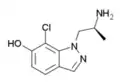

A number of related compounds are known, with a similar structure but having the indole core flipped and/or replaced with related cores such as indoline, indazole, benzothiophene, or benzofuran. These similarly are primarily active as agonists at the 5-HT2 family of serotonin receptors, with applications in the treatment of glaucoma, cluster headaches or as anorectics.

7-chloro-AL-34662 | 1-((S)-2-Aminopropyl)-7-chloro-1H-indazol-6-ol | 874881-86-4 |

|